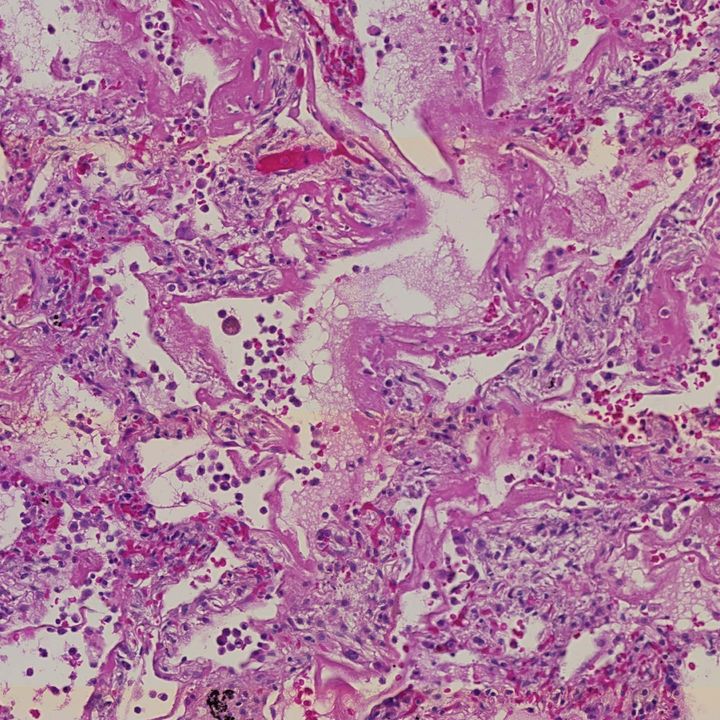

Researchers uncover cellular changes as damage to alveoli in the lungs progresses during COVID-19.

Changes in the cellular response during lung damage caused by SARS-CoV-2 – the virus behind COVID-19 – have been uncovered. Researchers reveal distinct phases where waves of immune responses give way to lung fibrosis – scarring of the lungs – in severe COVID-19.

As part of the UK Coronavirus Immunology Consortium (UK-CIC), researchers from the Wellcome Sanger Institute, Imperial College London, Newcastle University and Harvard University used a combination of cell mapping technologies to build a comprehensive understanding of the cellular response and lung tissue changes instigated during COVID-19.